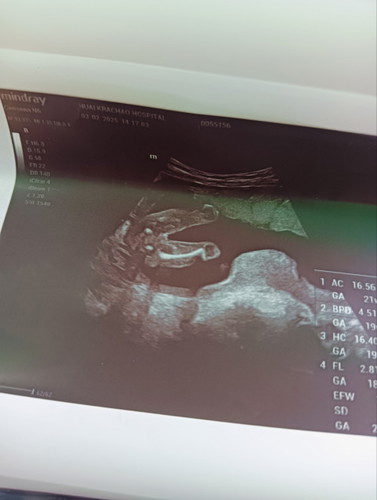

Girls or Boy

ได้ลูกสาวหรือลูกชายค่ะแบบนี้